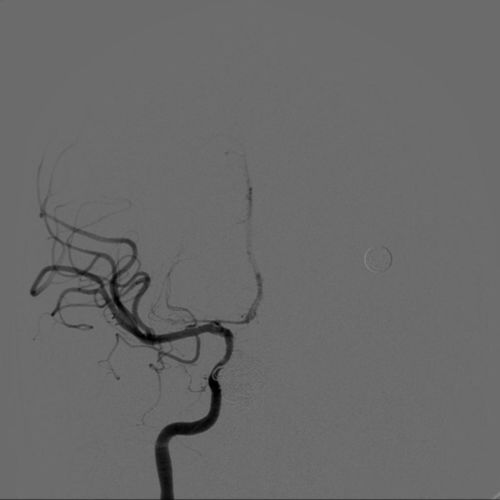

淫羊藿具有抗心肌缺血、改善冠脉血流及抗动脉粥样硬化等潜在作用,其有效成分淫羊藿酮可能有助于消除血管斑块。现代研究还表明,它可通过调节免疫、抑制血栓形成等机制改善心脑血管功能。